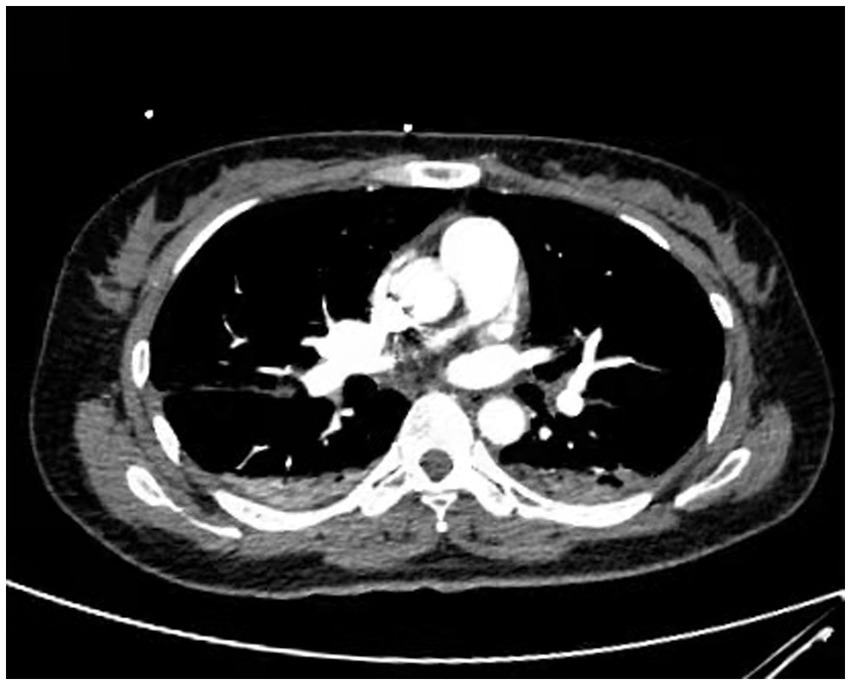

A 38-year-old married female with no previous history of cardiac disease, asthma, pneumonia, or allergies to food or medication presented with a ruptured ectopic pregnancy. On March 9, 2022, at 19:45, she underwent an emergency laparoscopic-assisted salpingectomy under general anesthesia at a local hospital. All preoperative evaluations, including laboratory tests, imaging studies, and physical examinations, were within normal limits. The surgery concluded at 21:00 without complications, and the anesthesia was satisfactory. Intraoperative fluid replacement included 1,000 mL of normal saline. At 21:10, the endotracheal tube was removed, and the patient was alert with no complaints. At 21:15, cardiac monitoring indicated a decrease in peripheral oxygen saturation (SpO2) to approximately 75%. The patient reported chest tightness and dyspnea, with pink frothy sputum. Physical examination revealed clear consciousness, tachypnea, and bilateral pulmonary rales. Immediate oxygen therapy via nasal cannula was started. Arterial blood gas analysis revealed: pH 7.31, partial pressure of arterial oxygen (PaO2) 83 mmHg, partial pressure of arterial carbon dioxide (PaCO2) 47 mmHg. A 12-lead electrocardiogram displayed sinus rhythm without signs of acute ischemia or infarction. After administration of 40 mg methylprednisolone and 20 mg furosemide intravenously, oxygen therapy was switched to a face mask, resulting in a SpO2 of approximately 95%. Due to ongoing chest tightness and dyspnea, the patient was transferred to our emergency department. Upon admission, the patient reported chest tightness and mild dyspnea. Vital signs were: temperature 37.3°C, pulse 100/min, respiratory rate 26/min, blood pressure 108/72 mmHg, SpO2 98% (with face mask oxygen). Physical examination revealed bilateral pulmonary rales, with normal cardiac and abdominal findings and no lower extremity edema. Non-invasive positive pressure ventilation was promptly initiated, along with 20 mg furosemide intravenously. Arterial blood gas analysis showed: pH 7.34, PaO2 127 mmHg, PaCO2 47 mmHg, white blood cell count 16.47*109/l, neutrophil percentage 96.6%, hemoglobin 107 g/L, platelet count 202*109/l, D-Dimmer 1.98 mg/L fibrinogen equivalent units, N-terminal pro-B-type natriuretic peptide 86.5 pg/mL. Chest computed tomography (CT) revealed bilateral pulmonary exudative changes consistent with pulmonary edema (Figure 1). After 6 h, the patient’s symptoms improved, with no dyspnea or chest pain and only a mild cough without sputum. Repeat arterial blood gas analysis showed: pH 7.46, PaO2 285 mmHg, PaCO2 45.9 mmHg. A follow-up chest CT at 12 h demonstrated significant resolution of the bilateral pulmonary exudative changes (Figure 2). Contrast-enhanced CT showed no evidence of pulmonary embolism (Figure 3). The patient’s respiratory status improved over the following days as the pulmonary edema resolved. She was discharged after 6 days without any complaints, and a final chest CT showed no significant abnormalities (Figure 4). A one-month follow-up revealed no residual symptoms.

Figure 3

Contrast-enhanced CT showed no evidence of pulmonary embolism. (Pulmonary embolism angiography reveals two areas of pneumonia-related changes and extensive alveolar pulmonary edema).